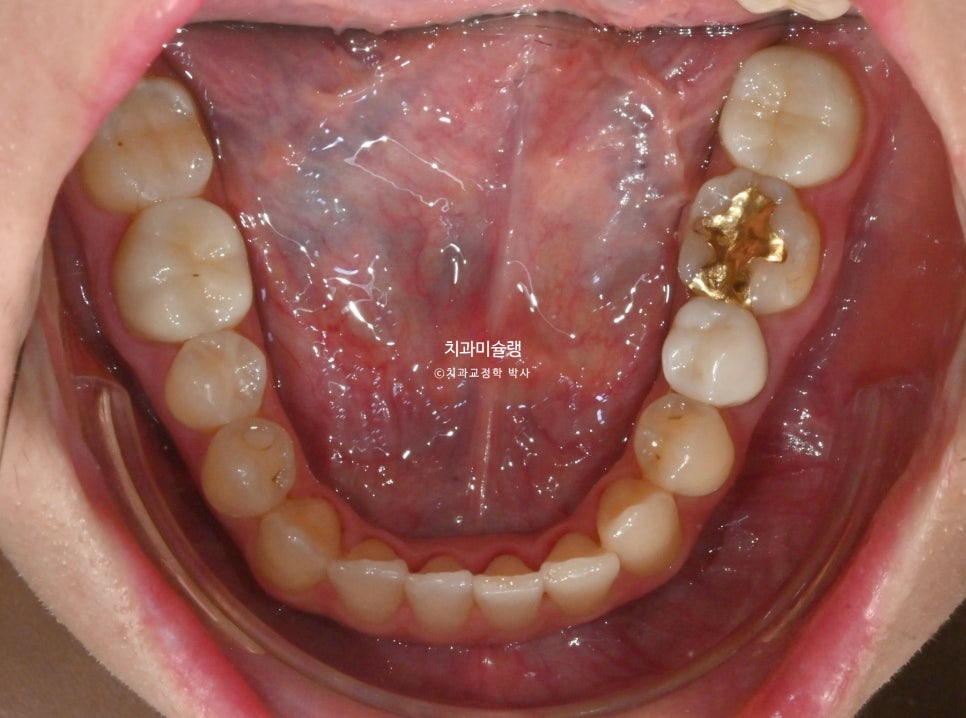

12월부터 2월까지 추가장치 7개를 모두 낀 후 모습입니다.

중심선이 맞아졌으며 송곳니를 포함한 위 6개 앞니 높이가 균일해졌습니다.

치열이 바르고 단차가 없이 높낮이가 균일해야 무삭제라미네이트도 균일한 두께로 제작이 됩니다.

무삭제 라미네이트는 두께가 엷은게 핵심이라 본래 치아색이 어느정도 비쳐 나오기 때문에, 라미네이트 두께가 들쑥날쑥 하면 색깔도 미세하게 얼룩덜룩 해집니다.